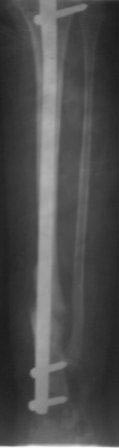

Уважаемые коллеги! помогите советом! Мальчик 2000 г.р. В 2007г получил перелом н/з костей правой голени, в районе лечили гипсом 6 месяцев, сращения нет, в обл.центре КДО аппаратом Илизарова - 3 месяца, после повторная деформация, в НИИТО КДО аппаратом Илизарова -7 месяцев, перелом якобы сросся, но после снятия аппарата через 2 недели после незначительной травмы повторный перелом. И родители начали лечиться у различных табибов и знахарей, мальчик не наступал, ходил с двумя костылями, одели различные ортезы и повязки, и нога сильно атрофировалась.(Мне кажется у ребенка был врожд. ложный сустав, латентная форма) , и в 2011 г, в октябре обратились к нам. , было произведена после рассверливания канала БИОС плечевым стержнем,но стержень пошел по мед.стенке дистального отломка поэтому остался некоторый вальгус(операция без ЭОП) ребенок через неделю начал самостоятельно ходить, клинически деформации нет, все обрадовались, выписали, повторно приехали только ч-з 1,5 года вот с такой деформацией, но ребенок ходит в школу, бегает, незначительно хромает, родители требуют исправить деформацию. Пока в голове один план: удалить стержень, закрытая остеоклазия, аппарат Илизарова из двух колец постепенная коррекция деформации, рассверливание к/м канала, БИОС плечевым стержнем (чуть длиннее), дистально по латеральному кортексу с использованием поллерных винтов и спиц. С уважением Абдурашид.

Сегодня сделал рентген, гвоздь сломался, видимо, усталостный перелом. Гвоздь и сломанная часть легко удалены, пока дистракционный остеосинтез аппаратом Илизарова, и будем постепенно исправлять деформацию. микрохирургия не доступна, оказалось, родители и повторный БИОС не могут из-за финансов,у читывая что ложный сустав не атрофичный и даже несколько гипертрофичный может продолжать аппаратное лечение? Или еще какие варианты? ,будем думать.